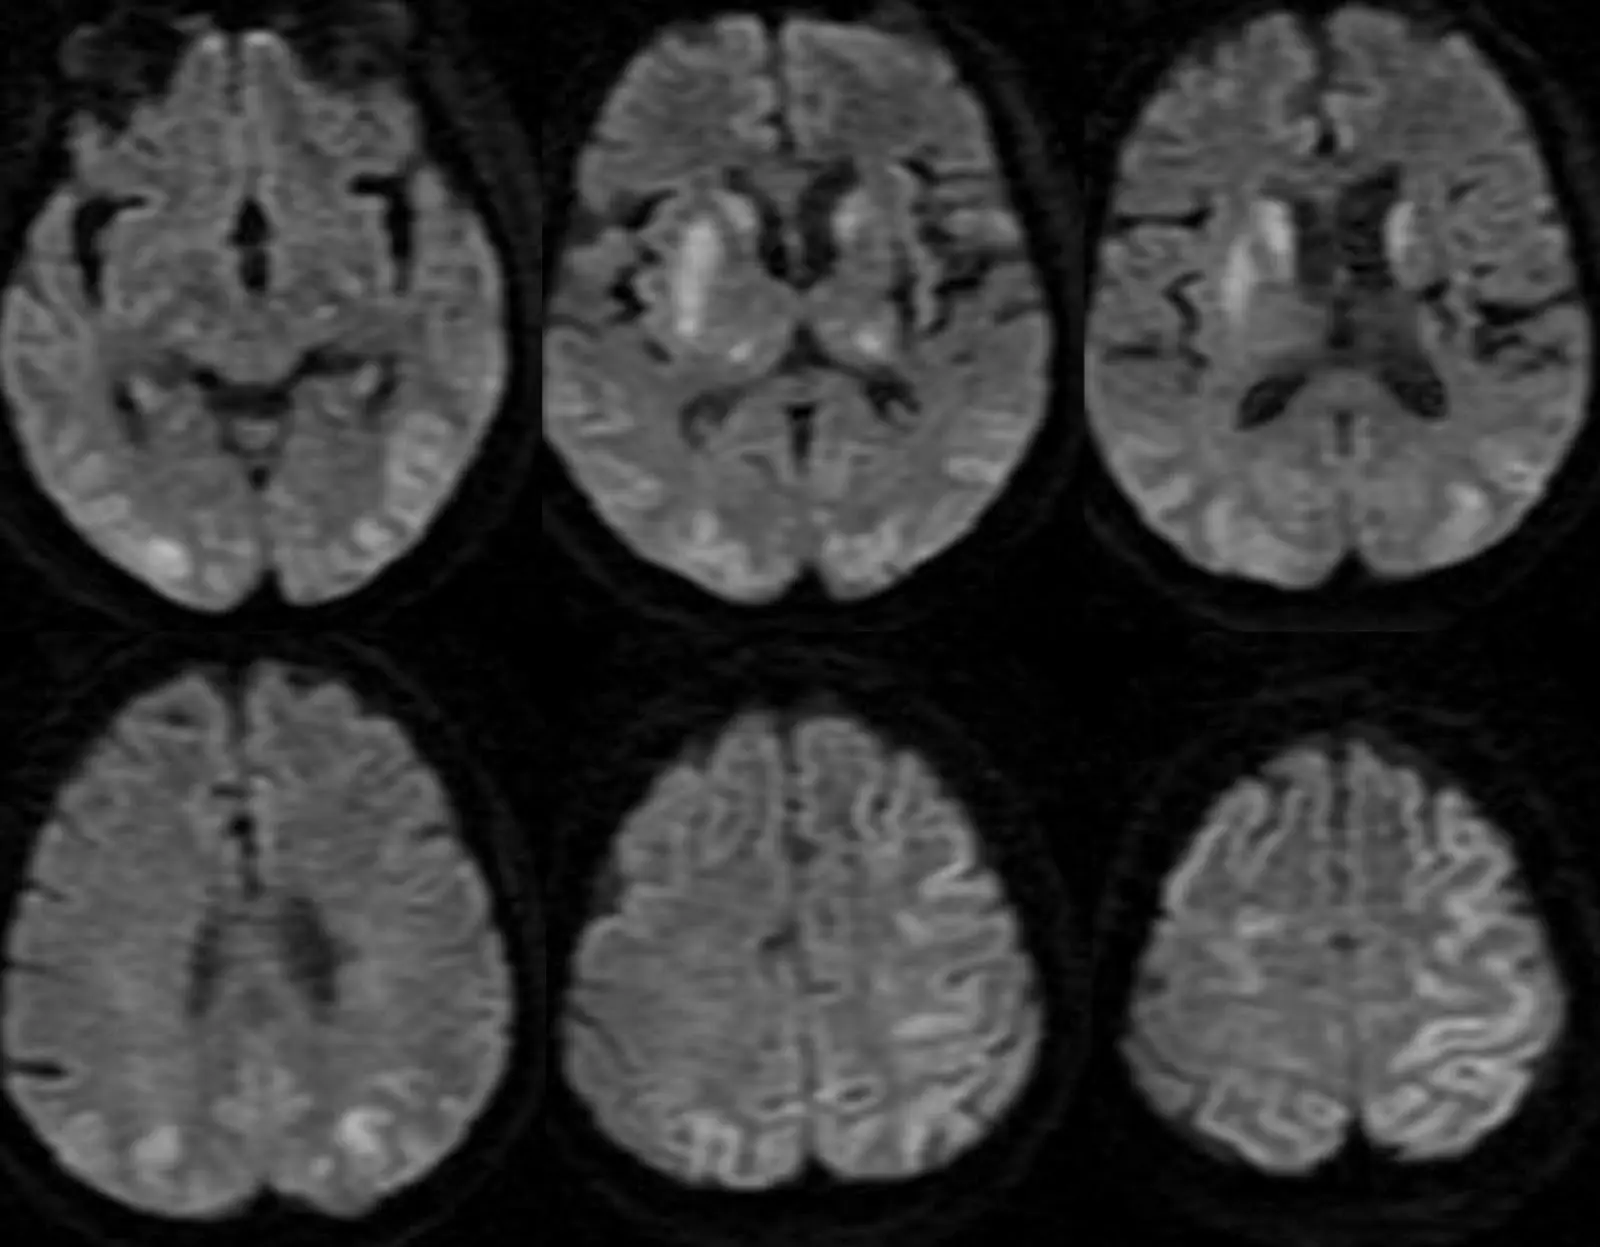

Dilansir dari Spinalcord.com, Hypoxia adalah suatu kondisi di mana jaringan tubuh manusia kekurangan oksigen, hal tersebut dapat menyebabkan seseorang yang mengalami hypoxia menjadi kesulitan untuk bernapas. Ada empat penyebab utama Hypoxia, yakni tidak ada suplai darah ke otak, pasokan darah ke otak sangat rendah, tidak ada oksigen darah, oksigen dalam darah sangat rendah.

Timeline dari hypoxia awal sampai kematian atau kerusakan otak memang sangat bervariasi. Kerusakan otak bisa dimulai dalam satu atau dua menit dari kekurangan oksigen total. Lima menit setelahnya, atau kematian sel otak, dan kerusakan otak parah yang menyertainya akan menjadi tak terelakkan.

Kebanyakan orang akan meninggal dalam waktu 10 menit setelah kekurangan oksigen total. Biasanya mereka yang punya catatatan kesehatan yang buruk akan meninggal lebih cepat. Beberapa orang mungkin akan terlebih dahulu mengalami serangan jantung ketika mengalami hypoxia.